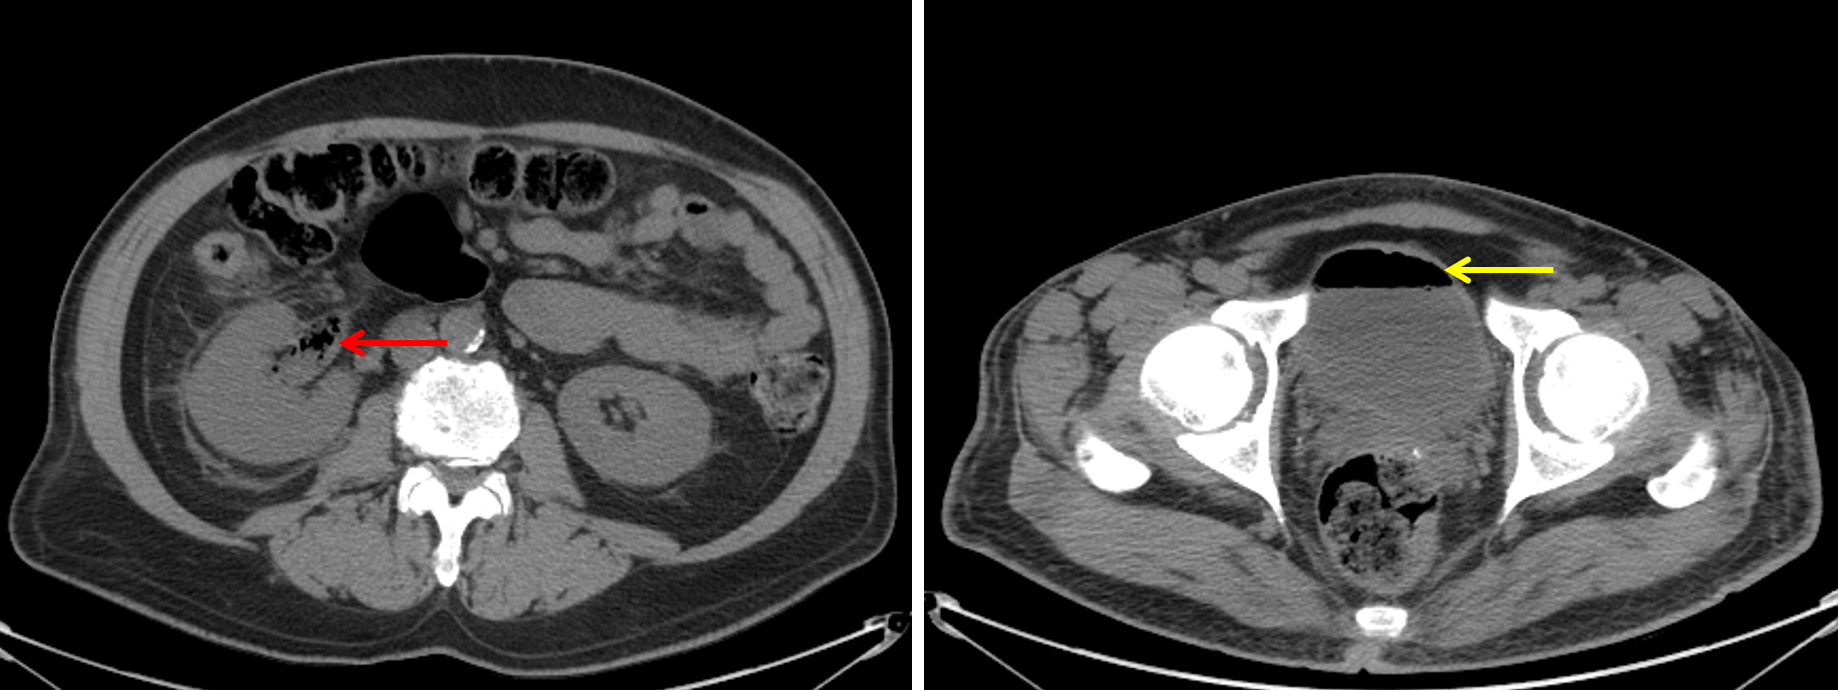

Ultrasound